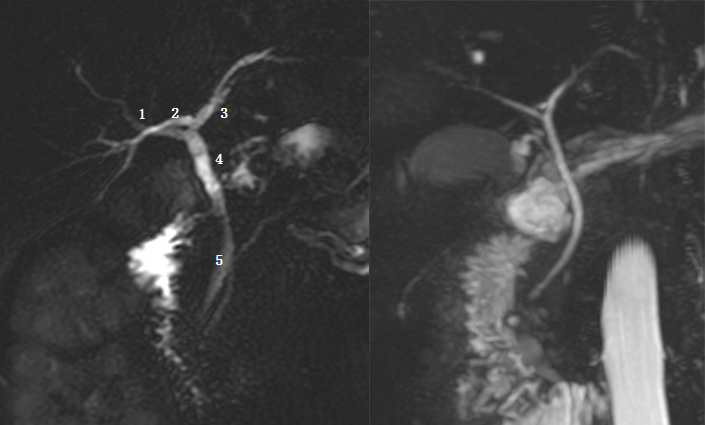

Ⅰ型:肝左右管汇合肝总管,胆囊管与肝总管汇合胆总管。左图:1 为肝左管,2 为肝总管,3 为胆囊管,4 为肝右管,5 为胆总管。黑箭头为胆囊结石。

Ⅲa 型:右后肝管汇入左肝管。左图:1 为右前肝管,2 为右后肝管,3 为肝左管,4 为肝总管,5 为胆总管。